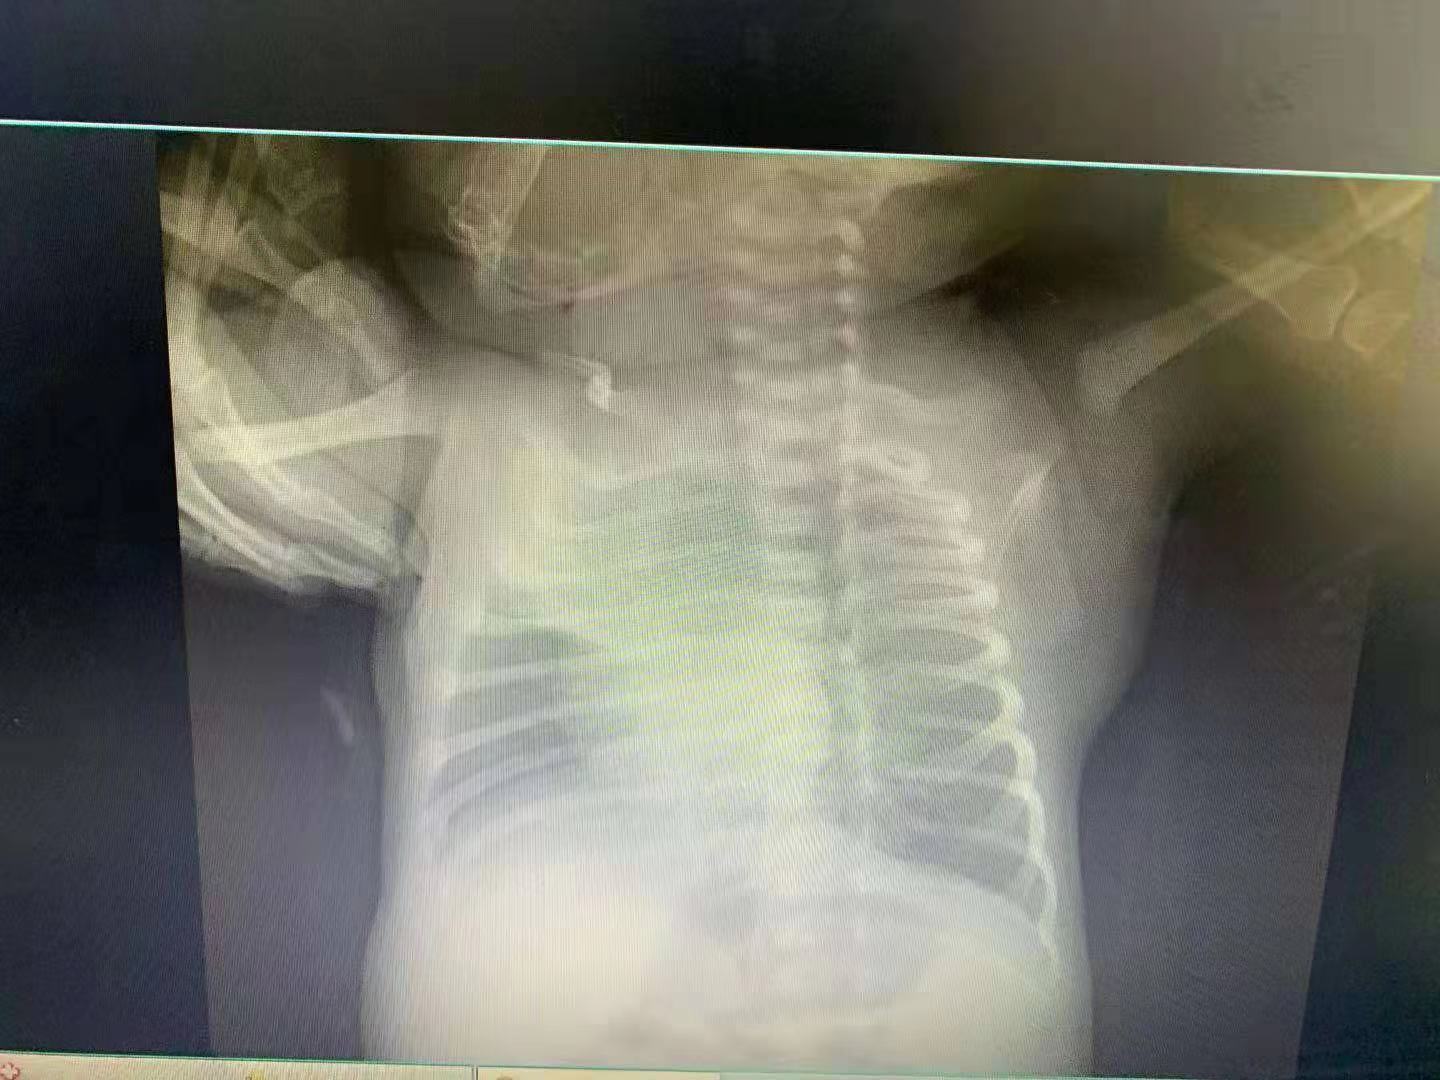

据家长们提供的医院诊断书显示,有婴儿被检查发现两肺存在“可见沿纹理走形模糊阴影”。“符合新生儿肺炎改变,请结合临床,建议抗炎后复查。”医院的检查报告显示。